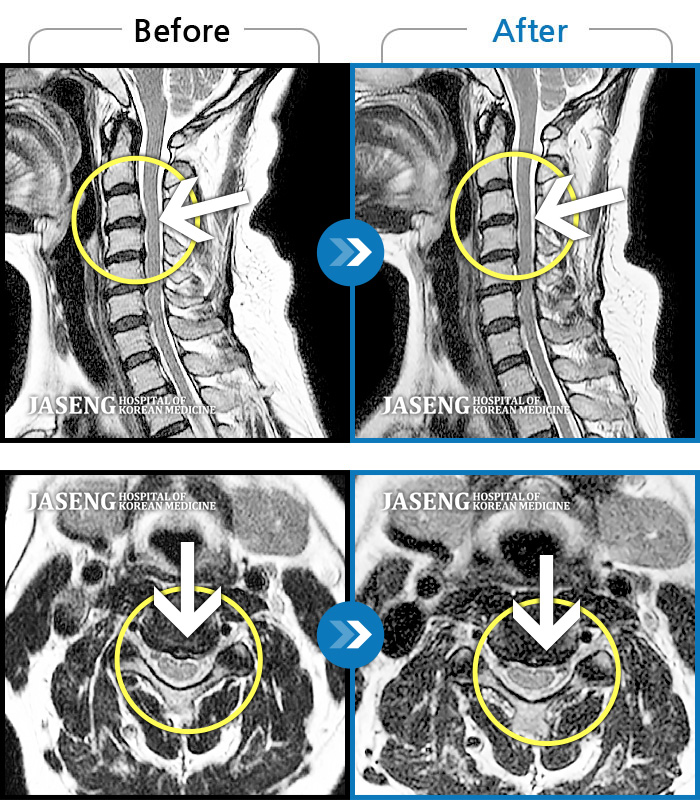

자생 비수술 한방통합치료 후

터진디스크가 흡수된 모습

비수술 치료만으로

터진 디스크 흡수

갑자기 발생한 목 통증과 좌측 손저림으로 고통스러운 상태

2021.02.16 ~ 2022.06.24

Before

After

날개뼈 안쪽의 통증으로 잠을 못 자고 양쪽 손(엄지)의 저림이 심해요.

2020.01.29 ~ 2021.01.05